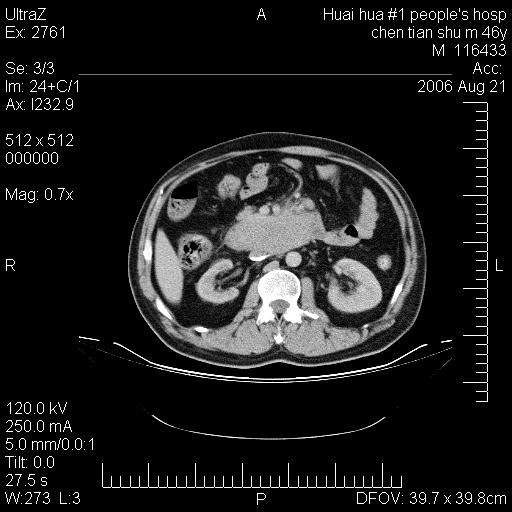

患者,男,46y。腹痛2月,消瘦。

十二指肠水平段占位,考虑间质瘤或平滑肌瘤。

肿块较大,腹膜后占位,境界欠清,周边脂肪密度较高呈条状影,有没有脂肪肉瘤可能,

缺少完整的三期图像。考虑肠系膜脂膜炎mp(肿块型)。

鉴别:间质瘤(这么大而无囊变不可思议)、平滑肌瘤/肉瘤、淋巴瘤、类癌,脂肪类肿瘤、转移瘤等。

十二指肠水平段占位,考虑间质瘤。

首先考虑小肠间质瘤。

十二指肠水平段软组织密度占位,考虑间质瘤可能性大。

腹膜后占位,境界欠清,考虑来源于十二指肠病变,间质瘤或平滑肌肉瘤可能性大。建议活检。

手术病理结果:原发性小肠恶性淋巴瘤(primary gastrointestinal lymphoma,pgil)是原发于胃肠的淋巴网织系统的恶性肿瘤,在结外淋巴瘤中居第一位,该病少见,临床无特异性,诊断困难,术前主要依靠影像学诊断。胃肠道本身具有较丰富的淋巴组织,因而胃肠原发性淋巴瘤是结外淋巴瘤最常见的部位,文献报道约占胃肠道恶性肿瘤的1%~4%,其中胃约占50%~70%,小肠约占35%~70%,结肠约占4%~6%。影像检查在pgil的诊断及分期中有重要的作用,ct是很有价值的检查方法。

胃肠淋巴瘤病理特点:胃肠道原发性淋巴瘤起源于胃肠壁固有层和黏膜下层的淋巴组织即胃肠粘膜相关淋巴组织(malt),多为粘膜相关淋巴瘤。病理上通常为非霍奇金淋巴瘤,且决大多数来源于b淋巴细胞,很少见于霍奇金淋巴瘤。胃肠原发淋巴瘤比胃肠道癌的发病率要低的多,最常见于胃,其病因可能跟幽门螺杆菌感染有关。幽门螺杆菌能引起胃粘膜损害,引起炎性及免疫反应,淋巴细胞聚集并形成滤泡,可影响胃的正常生理功能,导致胃淋巴瘤的发生。单纯性小肠淋巴瘤是常见好发于回盲末端,受累的肠段较长,可单发、多发,甚至累及整个小肠。原发性大肠淋巴瘤罕见,以直肠和盲肠最多见。病变大体观可表现为胃肠腔内外的肿块,也可表现为从黏膜下到浆膜面肠壁的纵向浸润,并且常常伴有肠系膜淋巴结肿大。任何情况下,肿瘤几乎总是导致一定程度的肠壁增厚,可对称或不对称,病变与正常组织间常无明确分界,肠腔可狭窄、正常或动脉瘤样扩张,后者主要是肿瘤在肠壁内浸润,破坏肠壁内植物神经丛所致。以上改变成为ct检测病变的病理基础。

肠道淋巴瘤的ct表现分为4类

1) 壁内浸润型, (2)多发结节型, (3)肠系膜受累伴腔外肿块型(本型就是),(4)肿块型。